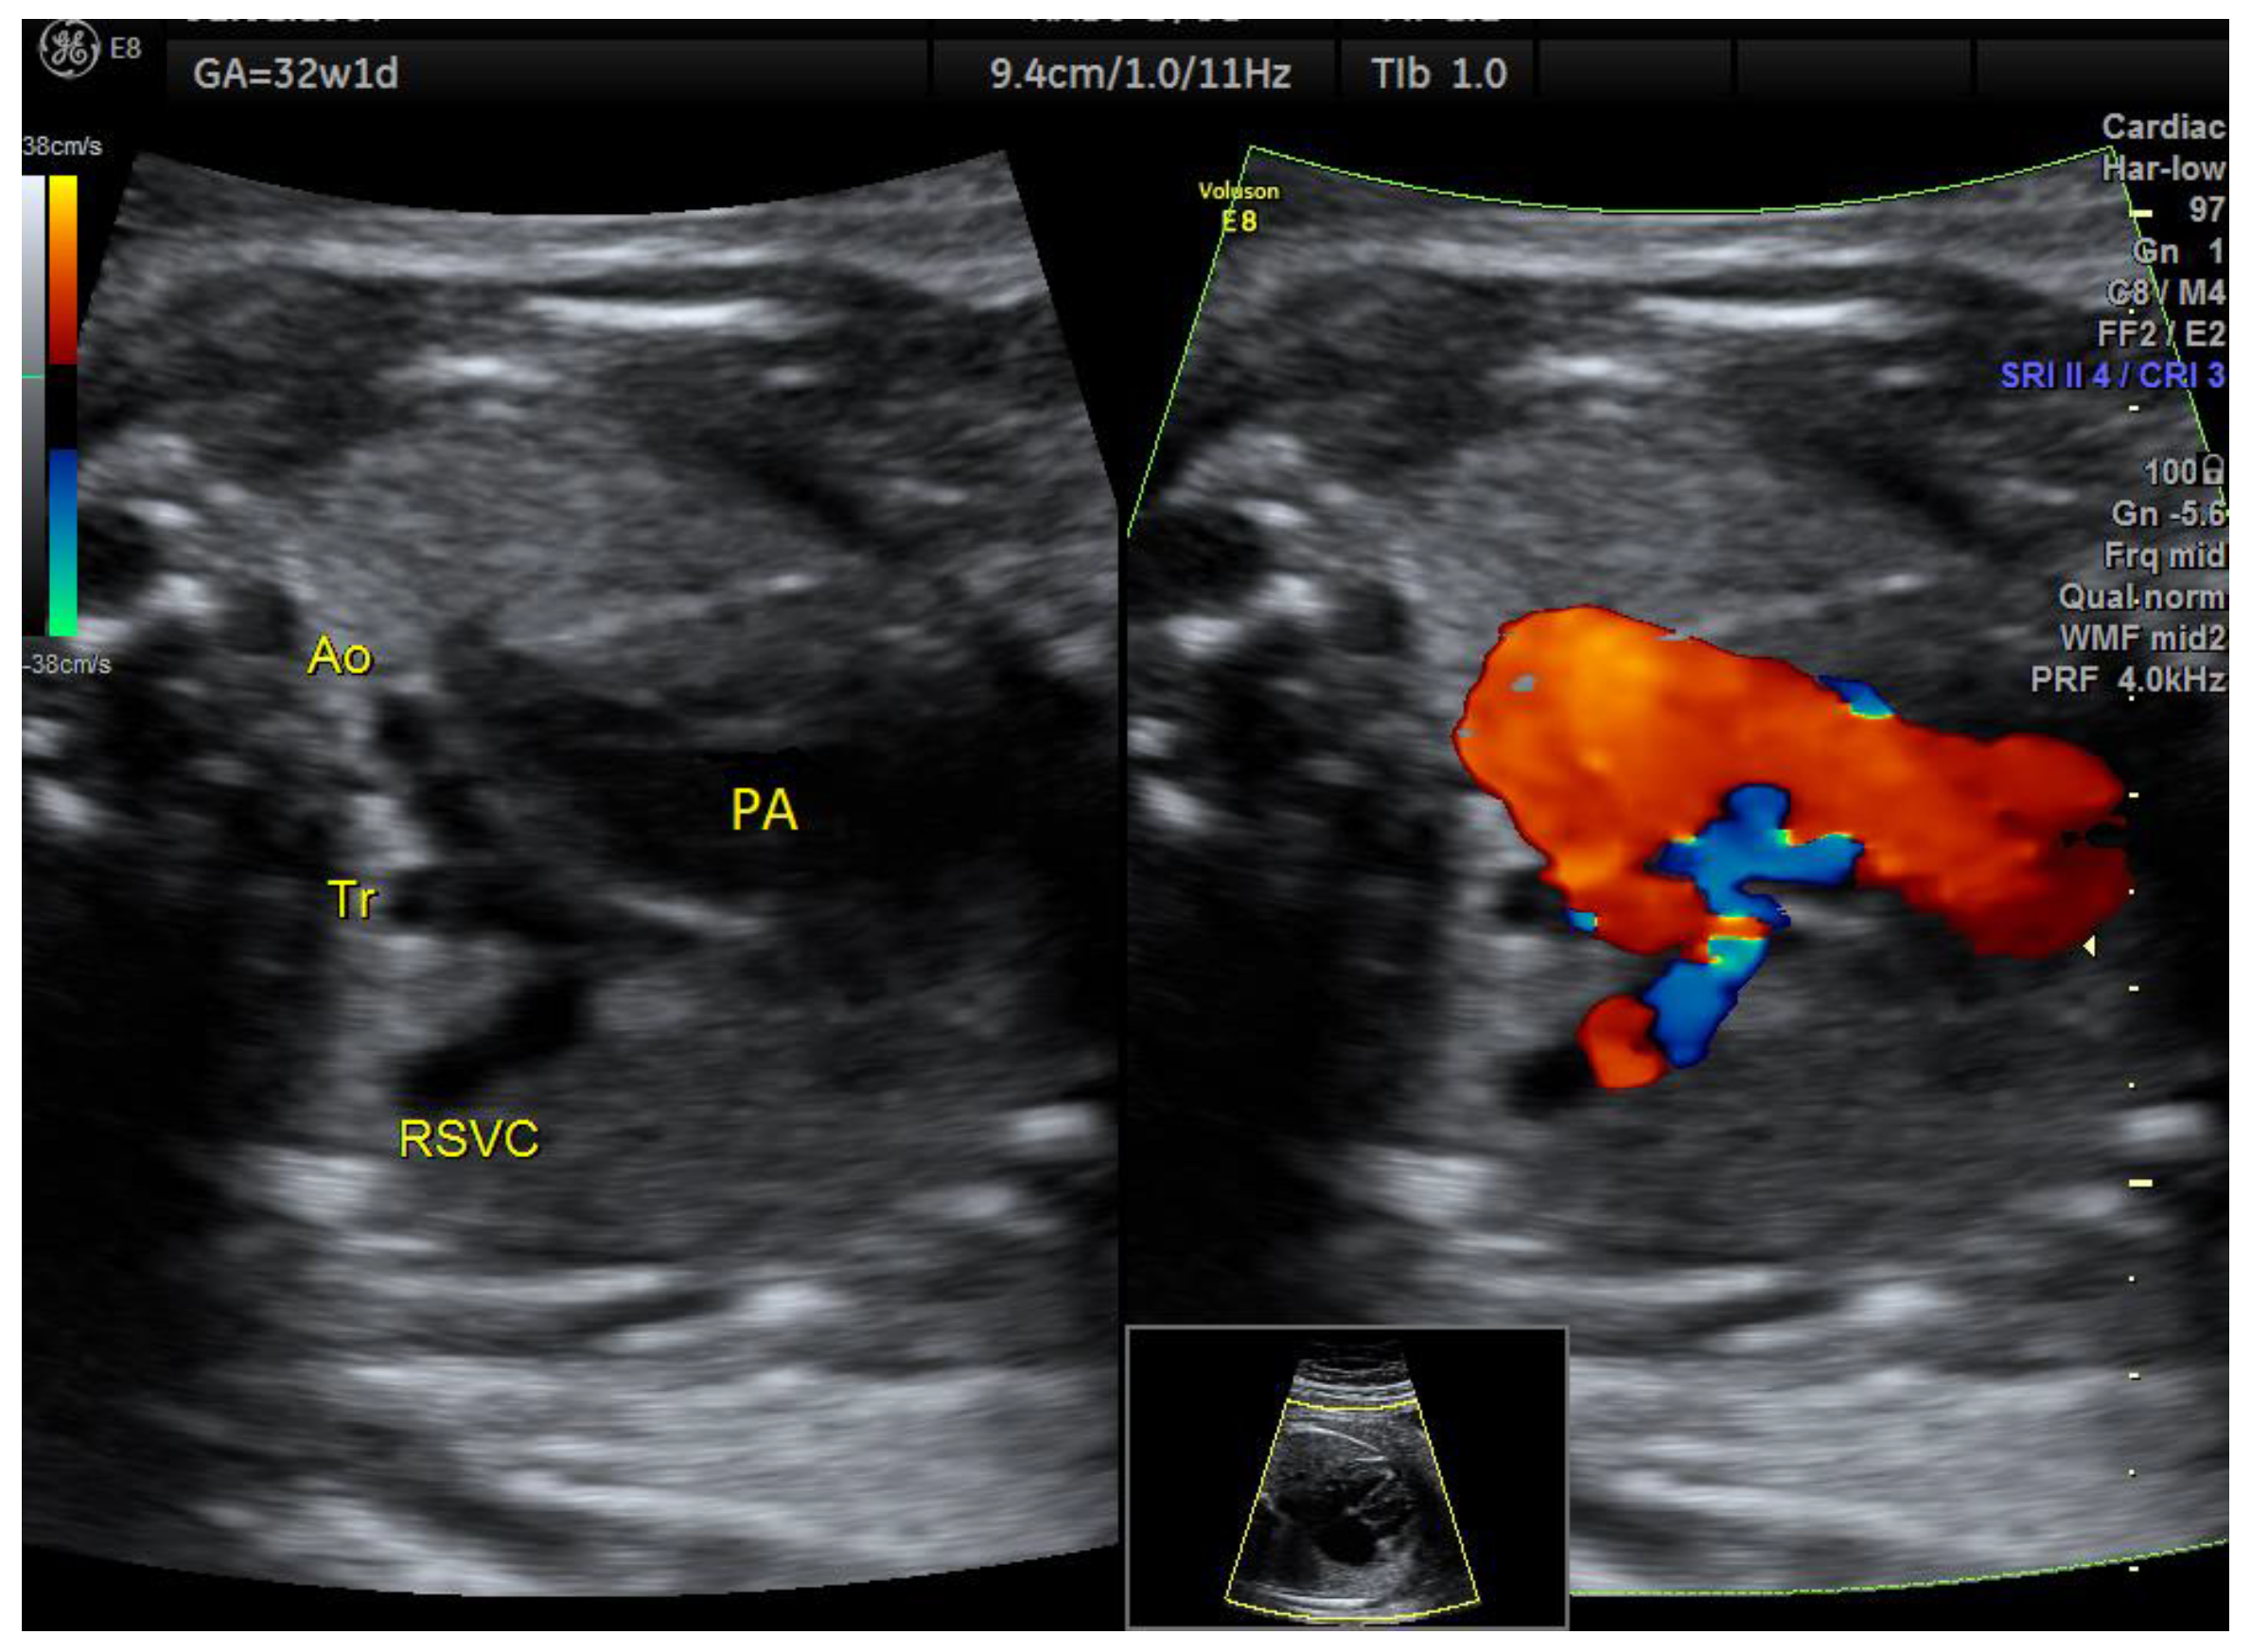

| Aortic coarctation | 3 | 1 × (hypoplastic NB and late FGR) | - | 3VT | + | 0 | 2 | 1 | 2/3 |

| IAoA | 1 | perimembranous VSD | - | 3VT | + | 0 | 1 | 0 | 1/1 |

| Fallot | 1 | - | - | 3VT | + | 0 | 1 | 0 | 1/1 |

| RAA | 1 | - | perimembranous VSD | 3VT | + | 1 | 0 | 0 | 1/1 |

| D-transposition 3 | 1 | - | - | 3VT | + | 0 | 0 | 1 | 1/1 |

| DAA | 1 | Tortuous DA at 20 w + late FGR | - | 3VT | + | 0 | 0 | 1 | 1/1 |